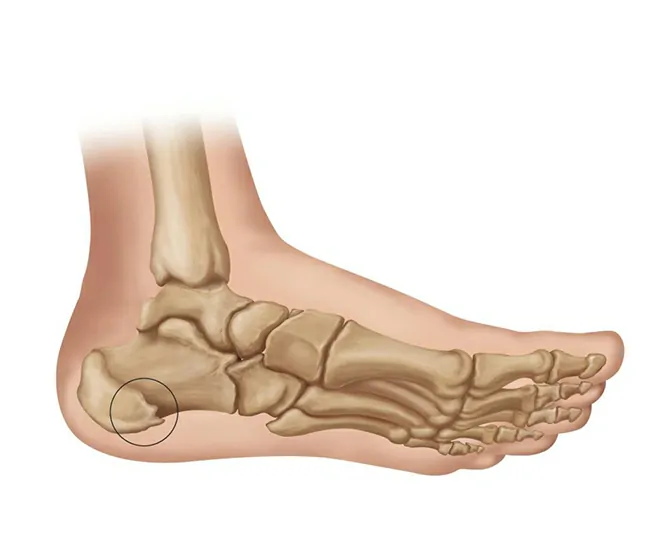

1. Calcaneal Spur – A bony growth (osteophyte) on the heel bone (calcaneus) due to prolonged stress.

2. Plantar Fasciitis – Inflammation of the plantar fascia, a thick ligament connecting the heel to the toes.